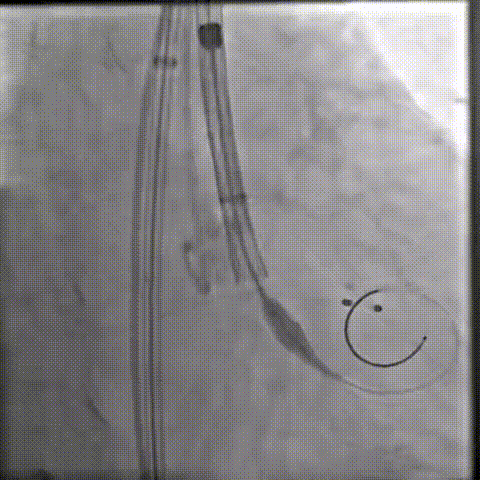

初始定位

释放瓣膜

80%工作位评估